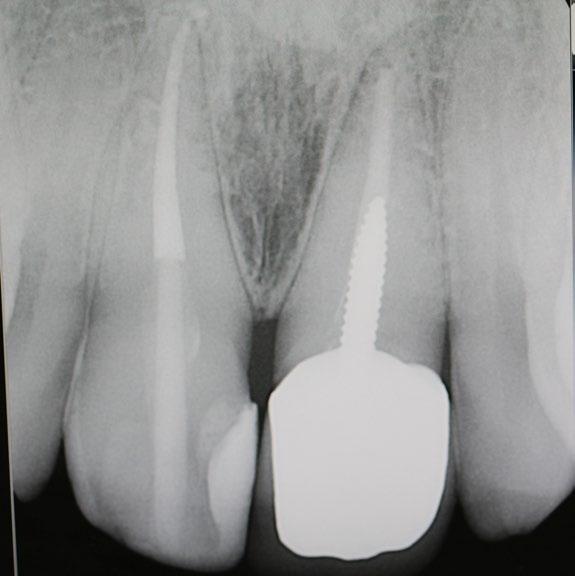

What are Dental Implants?

Dental implants are titanium posts surgically inserted into the jawbone, where they serve as a sturdy anchor for replacement teeth. Unlike dentures or bridges, which rest on top of the gums, implants integrate with the bone, a process known as osseointegration. This integration stabilizes the implant and makes it a permanent fixture in the mouth. The result is a replacement tooth that looks, feels, and functions like a natural tooth.

Implants act like natural tooth roots, promoting bone growth and preventing bone loss. Maintaining this bone structure not only supports facial features but also prevents the aging appearance that often accompanies tooth loss.

Long-Term Benefits and Oral Health

Dental implants also contribute positively to long-term oral health. They help preserve the jawbone and maintain the integrity of facial structures. When teeth are lost, the jawbone can gradually deteriorate because there is no tooth root to stimulate bone growth.

Moreover, unlike bridges and dentures, which often require the reduction of other healthy teeth to accommodate the appliance, implants do not compromise the health of neighboring teeth. This preservation of natural teeth is crucial for maintaining longterm dental health.